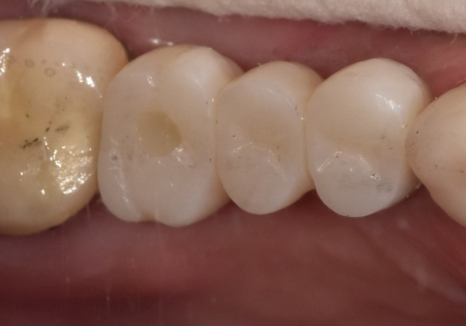

환자분께서는 이번 기회에

앞니의 모양과 색상을

더 가지런하게 바꾸길 원하셔서

총 6개의 치아(#13~23)를 연결하는

지르코니아 브릿지를 제작해 드렸습니다.